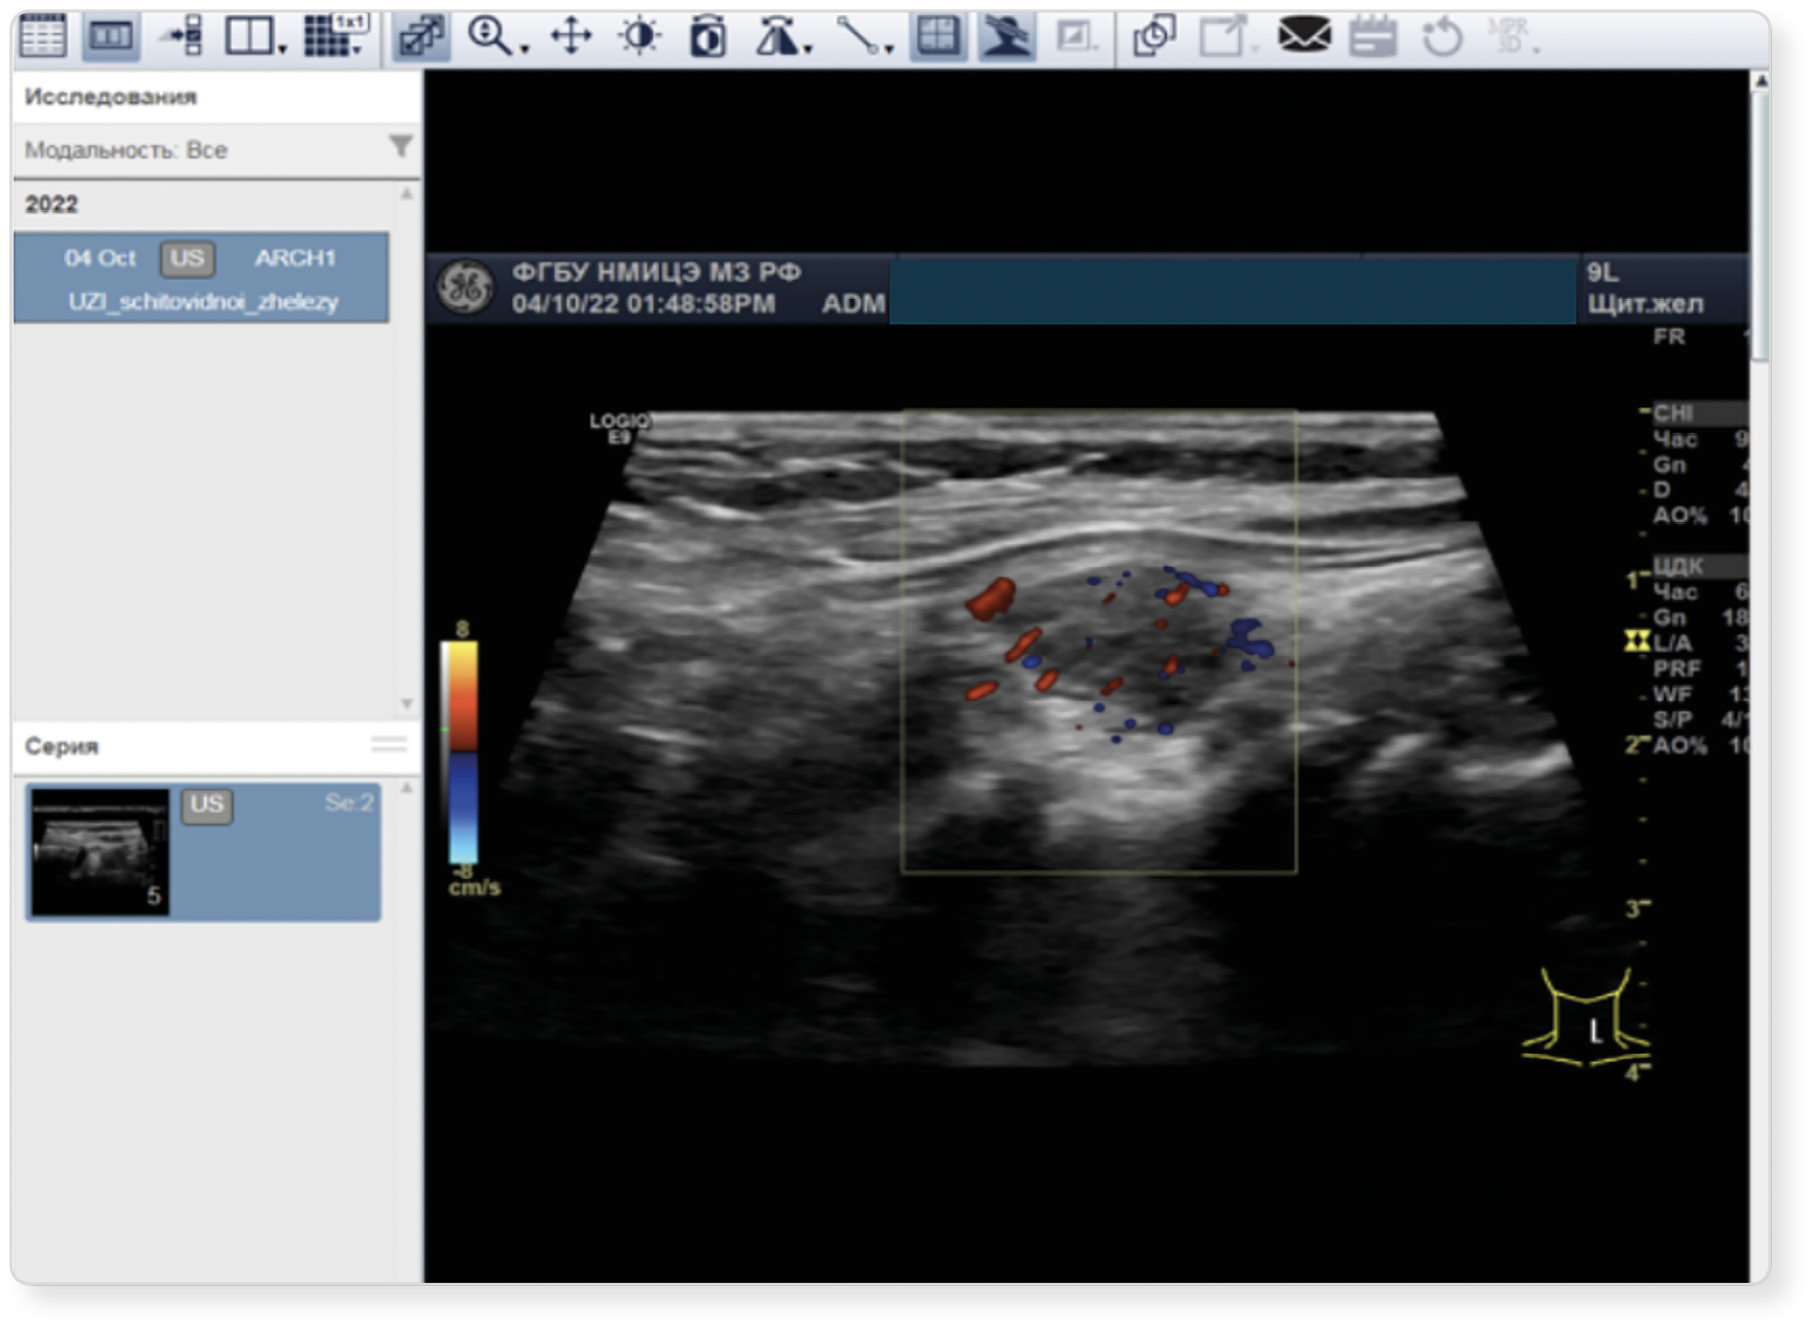

|  | 7. Рисунок 7. Выбор снимка с УЗ-аппарата. | |

| Тема | ||

| Тип | Исследовательские инструменты | |

|

Посмотреть

(205KB)

| Метаданные ▾ | |